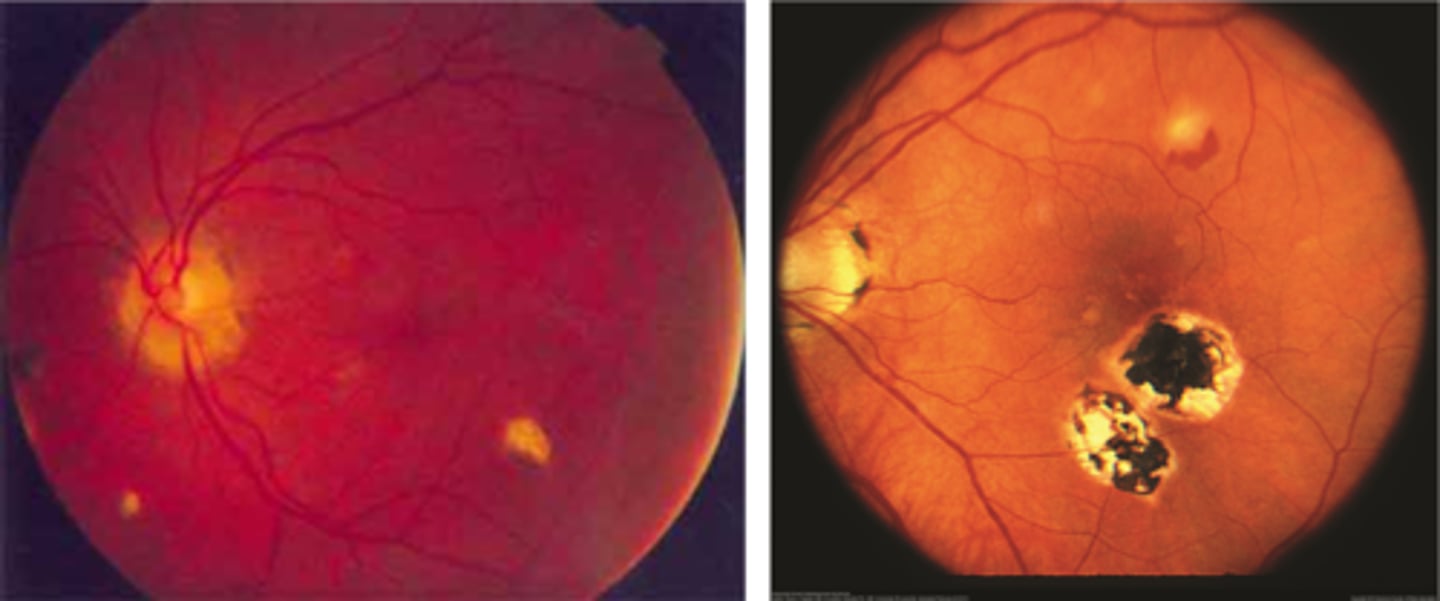

What findings of degenerative myopia are seen here?

PPA

crescent

lacquer cracks

What are lacquer cracks and what causes them?

breaks in Bruch's membrane that can expand and contract, mostly seen in degenerative myopia

How do lacquer cracks appear on fundoscopy?

jagged, irregular yellow lines showing sclera in the posterior pole

What is the main complication of lacquer cracks?

CNV in 29% of pt's